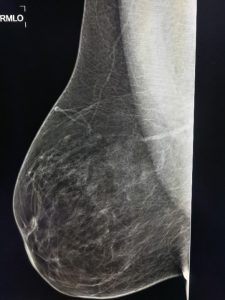

Η πυκνότητα του μαστού μπορεί να προσδιορισθεί με ψηλάφηση, αλλά κυρίως βασίζεται στην αξιολόγηση της σύστασης του μαστού, όπως αυτή απεικονίζεται στη μαστογραφία. Η εικόνα που δίνει ο λιπώδης ιστός στη μαστογραφία είναι πιο διάφανη και σκοτεινή. Αντίθετα ο μαζικός αδένας και ο συνδετικός ιστός εμφανίζονται ως ακτινοσκιερές (πιο φωτεινές) περιοχές.

Υπάρχουν διάφοροι τρόποι ταξινόμησης της πυκνότητας του μαστού. Συνήθως διακρίνονται τέσσερις κατηγορίες:

Κατηγορία 1η : Πολύ χαμηλή πυκνότητα μαστού – Αποτελείται κυρίως από λιπώδη ιστό.

Κατηγορία 2η : Ο μαστός αποτελείται κατά κύριο λόγο από λιπώδη ιστό, ενώ ανευρίσκονται διάσπαρτες περιοχές ινοαδενικών στοιχείων.

Κατηγορία 3η : Ετερογενώς πυκνοί μαστοί, με μεγαλύτερη αναλογία ινοαδενικών στοιχείων σε σχέση με τον λιπώδη ιστό.

Κατηγορία 4η : Ο μαστός αποτελείται σχεδόν εξ’ ολοκλήρου από αδενικό ιστό και χαρακτηρίζεται εξαιρετικά πυκνός.